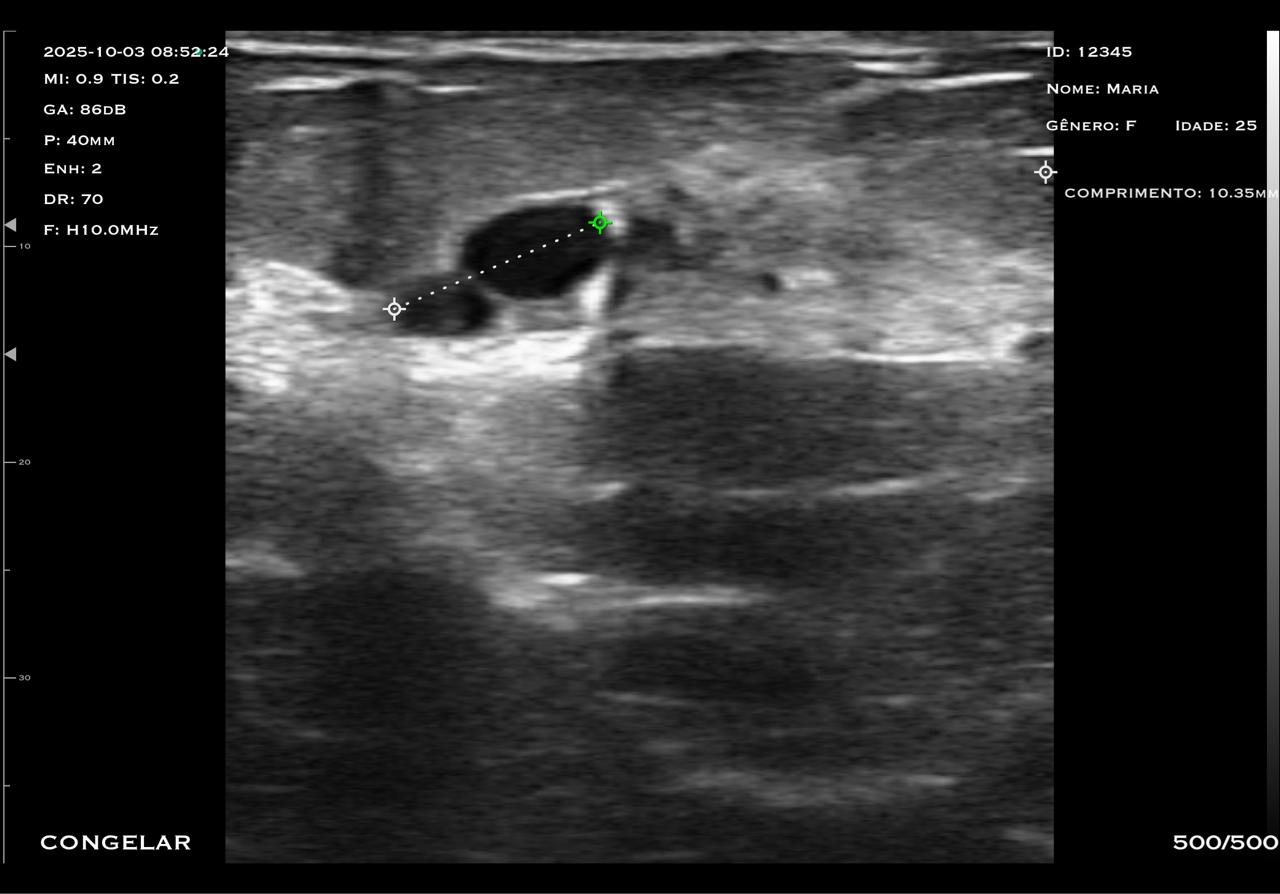

Com tecnologia linear e frequência de 7,5 a 10 MHz, o modelo M2HD é a escolha ideal para quem busca alta resolução em exames superficiais e intermediários, com foco em versatilidade e precisão.

O transdutor linear oferece imagens nítidas e detalhadas, permitindo a visualização precisa de estruturas como mama, tendões, músculos e articulações.

A frequência ajustável garante versatilidade para diferentes tipos de exames, desde avaliações mastológicas até procedimentos ortopédicos.

Possui modo biópsia com guia de centro, auxiliando profissionais que realizam procedimentos com agulha fora de plano além de indicar a angulação correta para procedimentos com agulha dentro de plano.